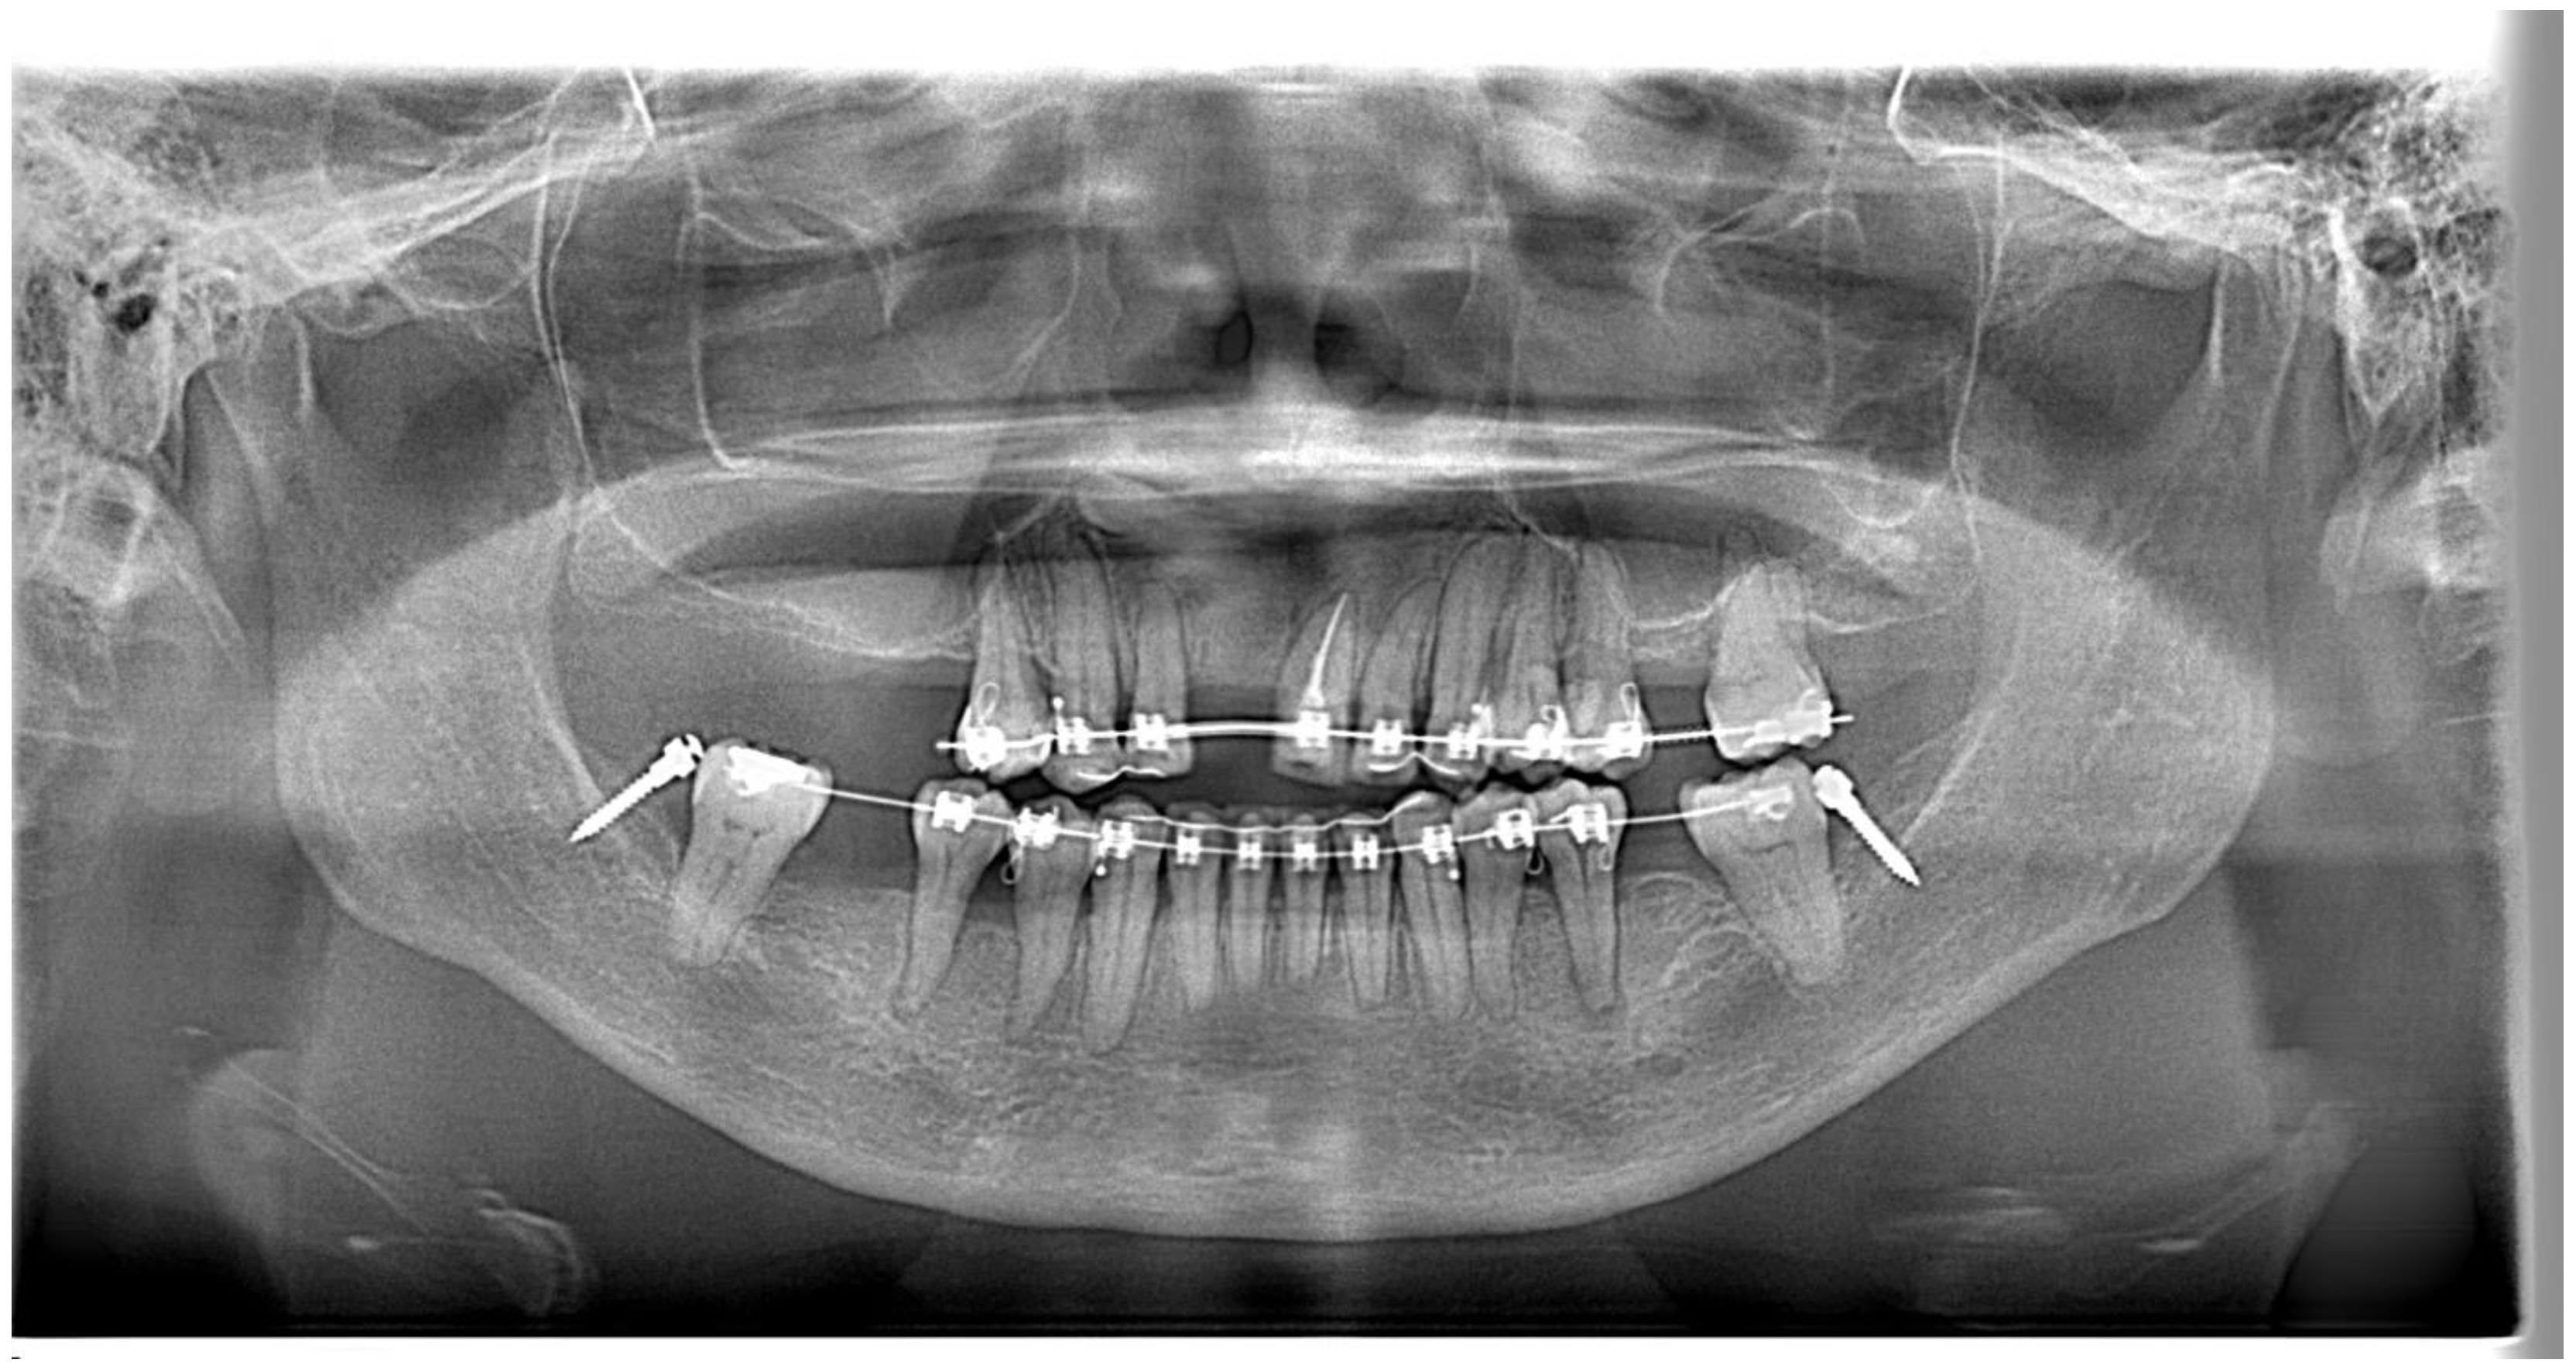

- The patient refused to surgically extract the supernumerary tooth as the supernumerary tooth was not associated with any pathology in the patient’s upper jaw for more than 59 years. The decision to keep the supernumerary tooth did affect the planned retraction of upper incisors. This meant that we could not retract the upper incisors as much as we had planned to based on the VTO. As a precaution, radiographs were taken regularly during the orthodontic treatment to ensure that there was no pathology with the supernumerary tooth and the supernumerary tooth did not affect the movement of the upper anterior teeth. As the mid-treatment orthopantomogram (Figure 12) showed that the root apex of tooth 23 was very close to the supernumerary tooth, we decided to stop further retracting the upper teeth.

- The first biomechanical challenge involves obtaining adequate dental anchorage for orthodontic movement, as patients often present with multiple missing teeth and reduced periodontal support due to periodontal disease [26]. In this case, the reinforcement of anchorage through alternative means, such as temporary anchorage devices (TADs) and using tooth 16 as free anchorage, was performed.

- The attempted placement of mini-screws on the upper alveolar bone resulted in dislodgement due to the low sinus floor. This was caused by sinus peumatization which was a continuous physiological process that increased the volume of the paranasal sinuses [43]. To address this, lower buccal shelf mini-screws were used instead to retract the upper arch with Class I elastics.